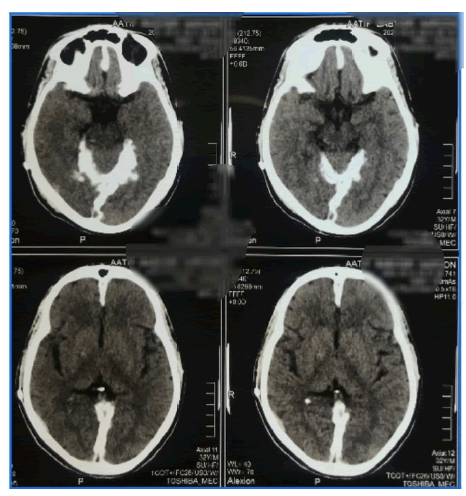

A 35 year old man with a 17 year history of epilepsy on Carbamazepine 400 mg once/daily with a rate of 4 seizures per year, the patient was referred from the neurosurgical department for controlling his seizures. Two years ago, he was diagnosed with hydrocephalus complicated by severe optic atrophy and underwent insertion of a ventriculoperitoneal shunt. Prior brain imaging (CT/MRI) (Figures 1-3) revealed the existence of hydrocephalus and heavy meningeal calcification. The patient had no other symptoms suggesting motor, sensory, cerebellar, sphincter and autonomic abnormalities. There was no past history of head trauma, childhood cerebral infection or skin tumors. He is neither diabetic nor hypertensive, and has a negative family history for both conditions.

neurological-ct

Figure 1. CT brain reveals falx cerebri and supratentorial dural calcification.